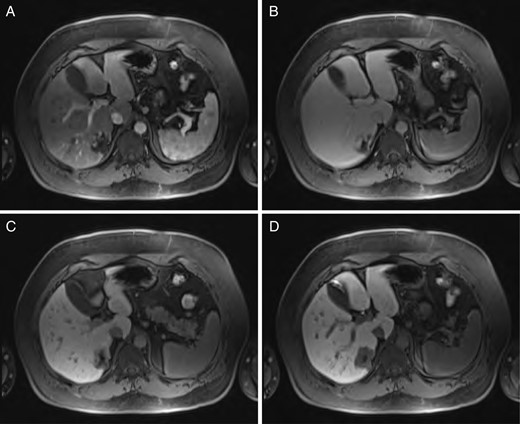

A 40-year-old male underwent computed tomography (CT) scan of the chest for atypical chest pain, which revealed an indeterminate 3-cm lesion in the right liver. He subsequently underwent triple-phase CT, which revealed two separate lesions: a 4.3 × 5.3-cm discrete mass in the left liver (Segment 2) and a 2.3 × 3.7-cm lobular, partially exophytic hypodense lesion in the right liver (Segment 6). On the delayed phase, the periphery of the right posterior hepatic mass was isodense with the rest of the liver parenchyma, but the central portion remained hypodense. Based on these findings, the right-sided lesion was felt to be a hemangioma, but the findings were still inconclusive regarding the left-sided lesion. Magnetic resonance imaging (MRI) was performed with intravenous gadoxetic acid, a hepatocyte-specific contrast agent. The lesion in Segment 2 was hypointense on precontrast T1, hyperintense on T2-weighted images, and showed avid enhancement on the arterial and portal venous phases. There was a delayed washout on the hepatographic phase. Although nonspecific, this was felt to be most consistent with an adenoma. The right-sided lesion showed postcontrast gradual enhancement with centripetal fill-in, reinforcing the diagnosis of hemangioma (Figs 1 and 2).

Sequential MRI imaging of HSFT: (A) T1 arterial phase, (B) T1 60-s delay phase, (C) T1 postcontrast phase and (D) T1 hepatographic phase.